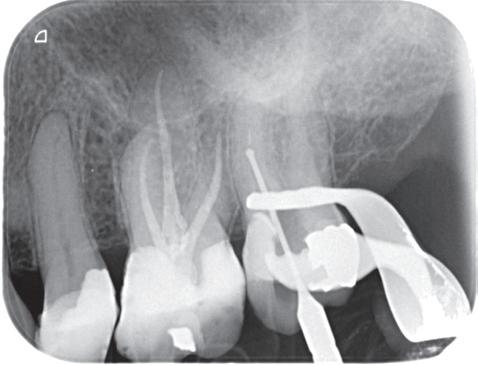

De verwijzend tandarts is bezig om een wortelkanaalbehandeling uit te voeren in gebitselement 27. Er zijn vier kanalen gevonden, maar helaas breekt er in het mesiobuccale kanaal (MB 1) een WaveOne vijltje af, maat geel (foto 2). Het lukt de tandarts niet om

het vijltje te verwijderen. De patiënte wordt verwezen voor het afmaken van de wortelkanaalbehandeling.

Als ik de patiënte zie, valt me op dat de opening die de tandarts gemaakt heeft, nogal klein is (foto 3). Eigenlijk is daar niet zoveel reden toe; als ik een ideale opening inteken (in rood), dan loopt een groot deel door restauratiemateriaal. Overwogen kan worden om de aanwezige mesiale box met restauratiemateriaal weg te halen als dat het zicht op de pulpakamer vergroot – ik verwijs naar de tip hierboven (wees bij het openen niet spaarzaam met het wegnemen van aanwezig restauratiemateriaal).

Het afgebroken instrument ligt vrij diep; in het onderste 1/3 deel van de wortel. Vaak laten we het afgebroken instrument in het onderste 1/3 deels zitten, omdat verwijderen lastig is en er een kans is op schade. Daarom proberen we het te passeren en wordt het afgebroken instrument onderdeel van de kanaalvulling.

Passeren lukt mij in deze casus helaas niet. Omdat het instrument in een recht deel van het kanaal ligt, waag ik een poging om het afgebroken instrumentje te verwijderen, zodat ik het kanaal kan desinfecteren en kan vullen.

Onder microscopie en met een LN boortje zoek ik het instrumentje op. Na verificatie verwijder ik het door

met een ultrasone tip (Spartan CPR 8, bruin) rondom het vijltje materiaal weg te nemen, waardoor deze als het ware uitgegraven wordt. WaveOne vijltjes zijn irritant om te verwijderen, het nikkeltitanium materiaal wil naar een oorspronkelijke vorm (een rechte vorm) terugbuigen en daarom drukt het zich steeds vast bij het verwijderen. Staal is vaak makkelijker te verwijderen. Maar het lukt me en de wortelkanaalbehandeling kan worden afgemaakt.